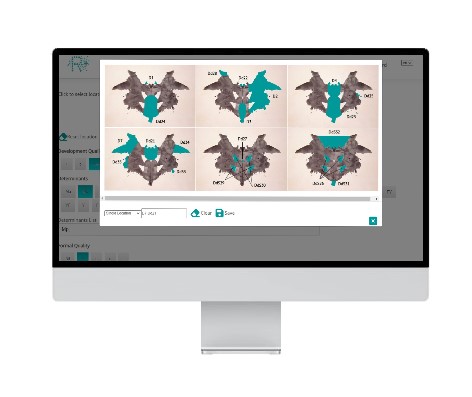

Rorschach-Plus

The web based administration and coding for the Comprehensive System.

Our user-friendly and intuitive surface allows you to use r-plus during and after the administration. You can choose between Just Coding or Administration and Coding!

Learn more+Innovative Client Specific Structural Summary and Sequence of Scores

Clearly laid out and easy to interpret Structural Summary and Sequence of Scores with just one click!

Create reports at the push of a button!